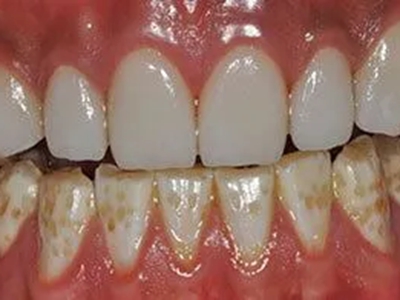

牙釉质发育不全牙表面上有坑图

牙釉质发育不全发展到严重时,导致牙釉质表面缺损,表现为带状、窝状的褐色凹坑,容易积存食物残渣诱发龋齿,表现为牙齿边上出现深褐色小洞。

牙釉质发育不全牙齿变薄图

牙釉质发育不全患者的牙齿有色泽和透明度改变,表面出现白垩色釉质,同时牙齿顶端变透明、变薄,但患者可能无敏感、疼痛等自觉症状。